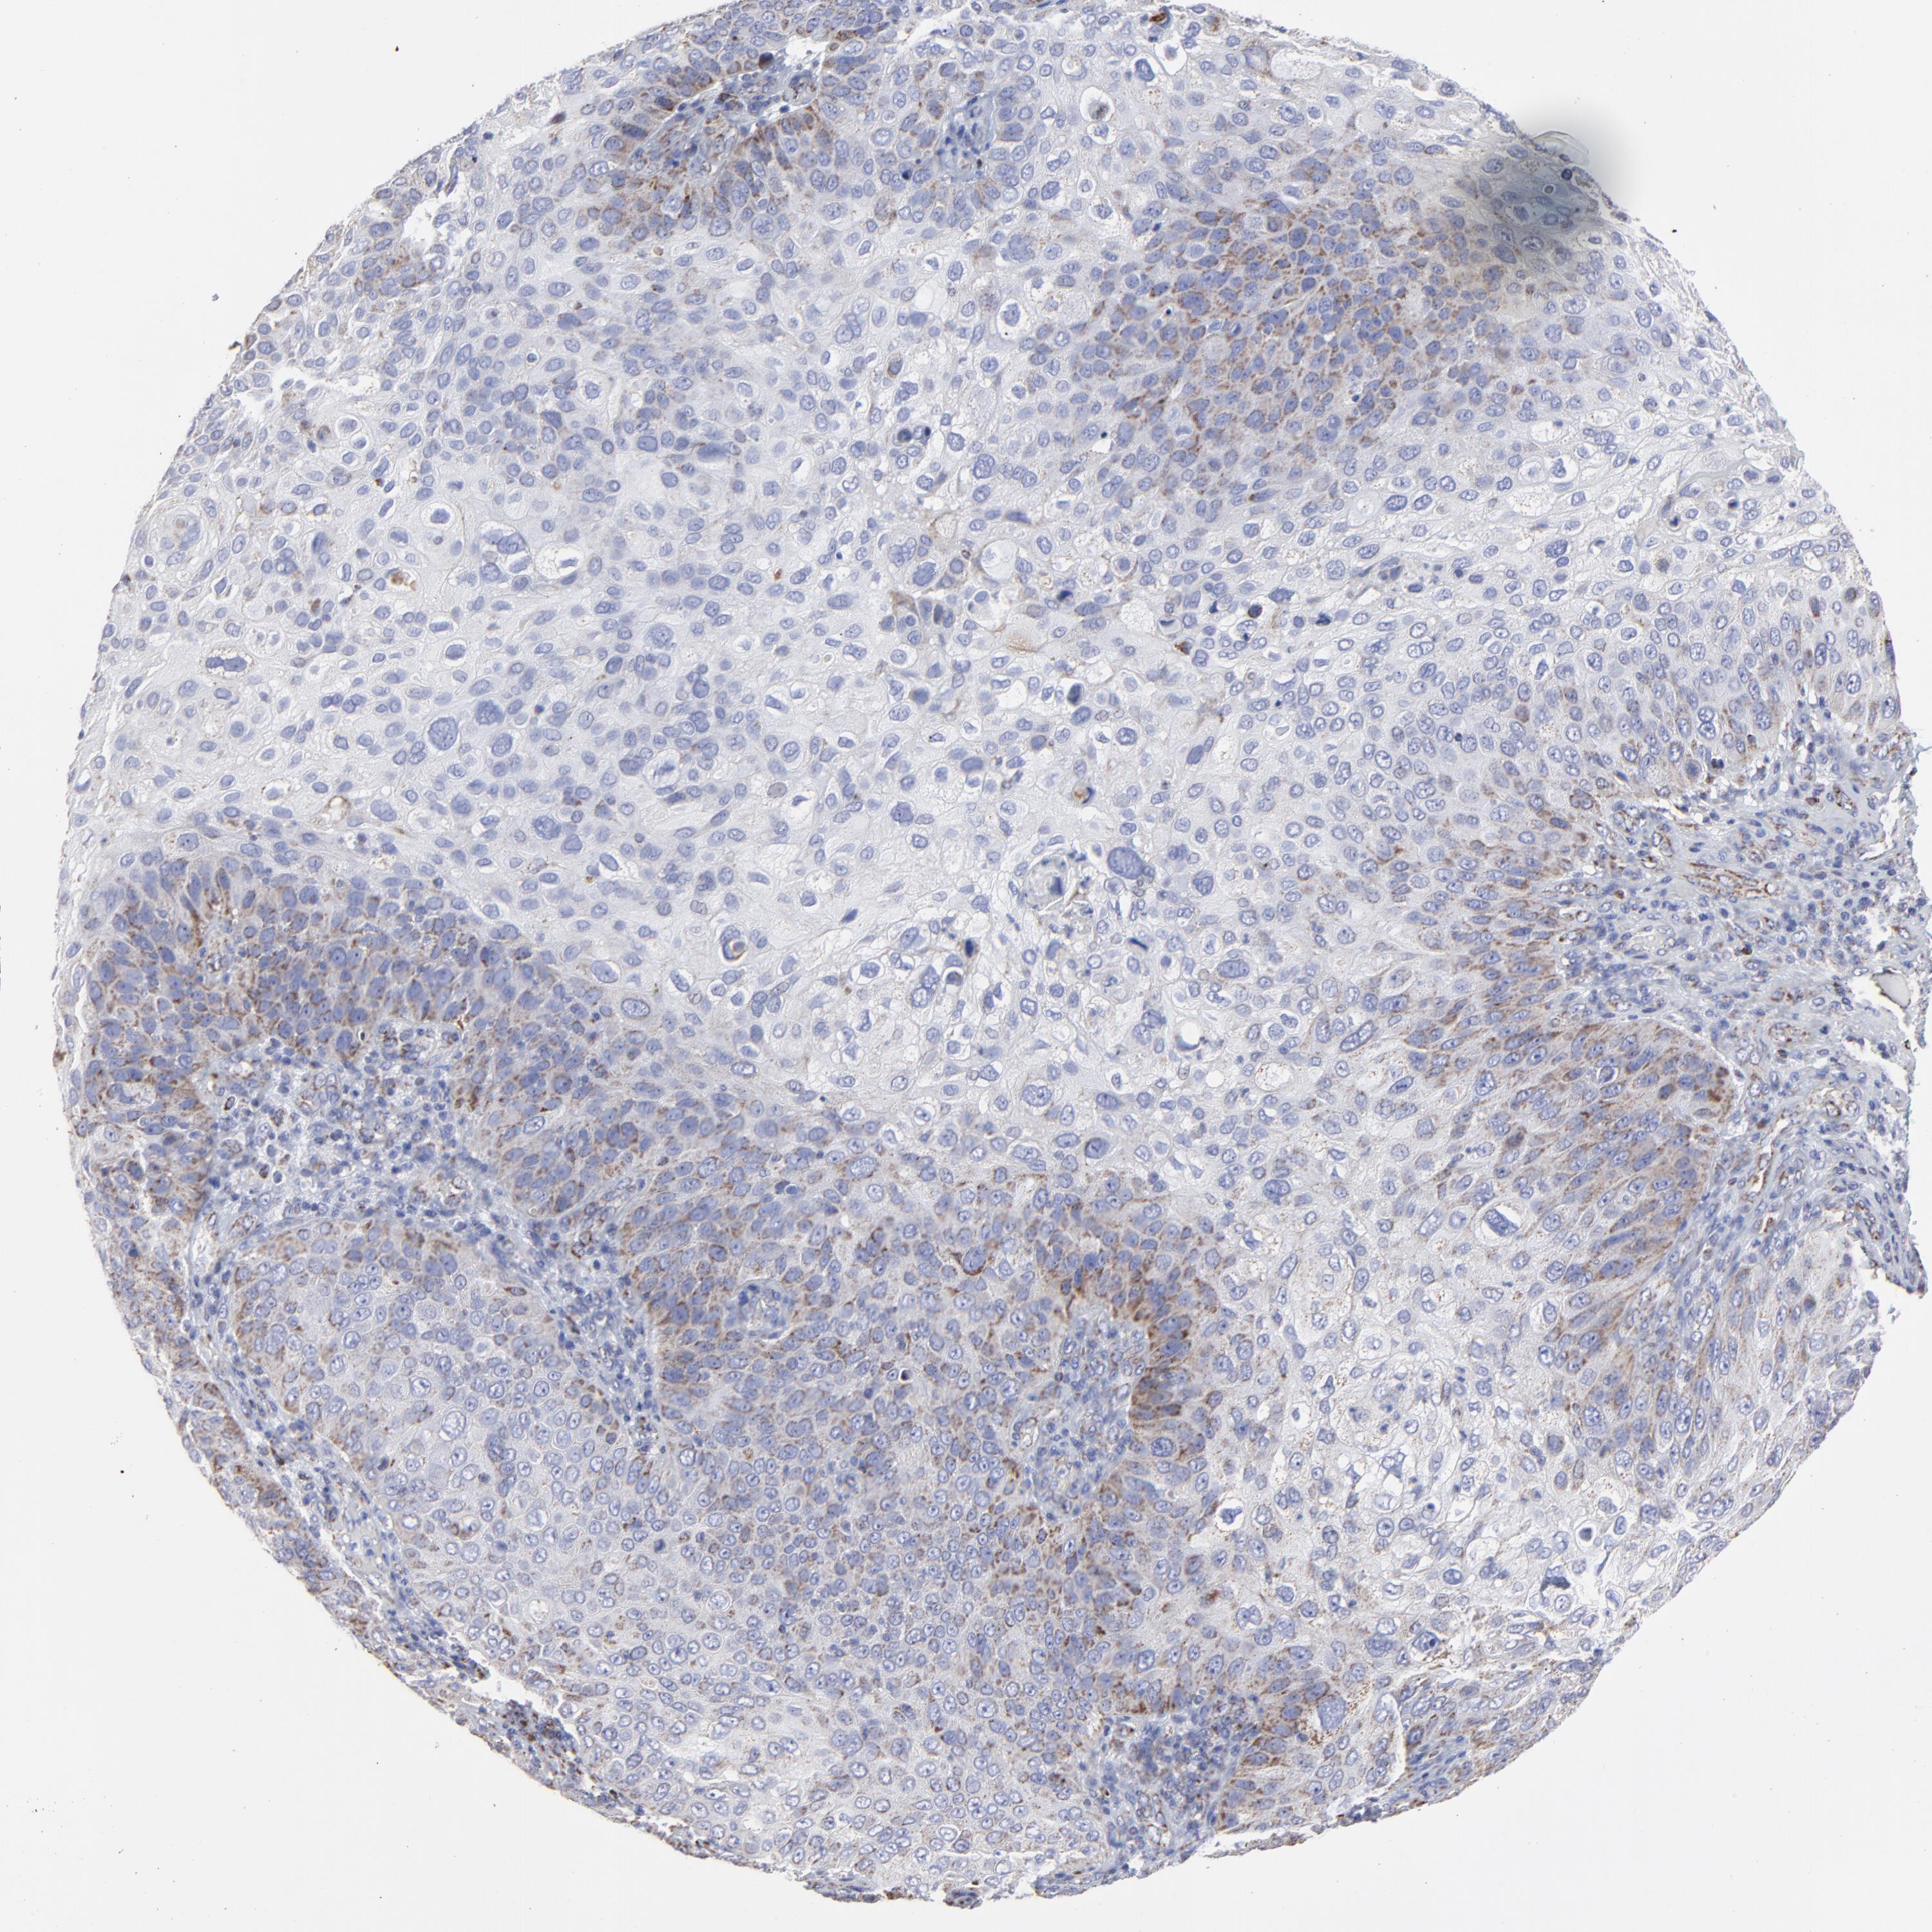

SKIN CANCER - Protein expressioni

A mouse-over function shows sample information and annotation data. Click on an image to view it in a full screen mode. Samples can be filtered based on level of antibody staining by selecting one or several of the following categories: high, medium, low and not detected. The assay and annotation is described here.

Antibody staining in the annotated cell types in the current human tissue is reported as not detected, low, medium, or high, based on conventional immunohistochemistry profiling in selected tissues. This score is based on the combination of the staining intensity and fraction of stained cells.

Each image is clickable and will lead to virtual microscopy that enables deeper exploration of all samples and also displays staining intensity scores, fraction scores and subcellular localization as well as patient and tissue information for each sample.

Basal cell carcinoma